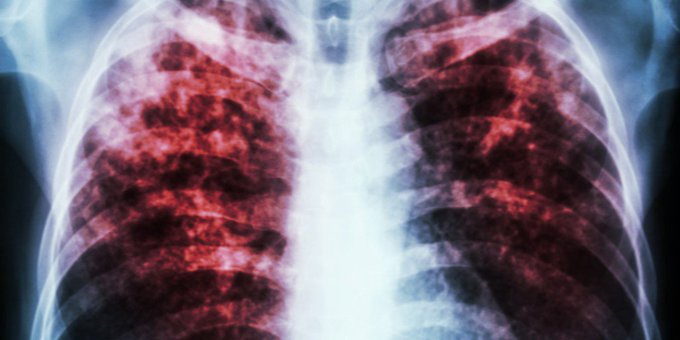

¿Cuáles son los síntomas de la #tuberculosis y cómo se trata? Aquí lo que debes saber ow.ly/FrHL50wg3ZV